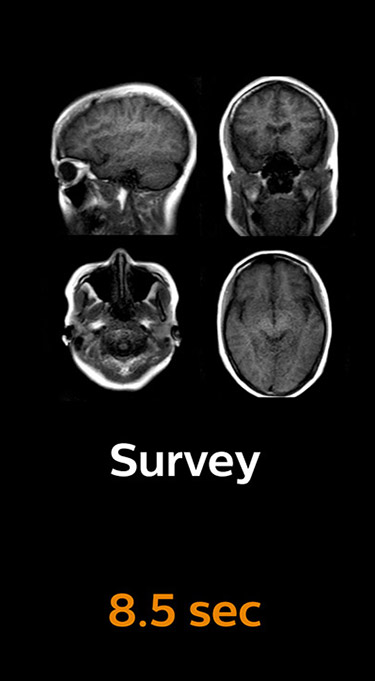

With Compressed SENSE, the scan time for the routine cervical spine examination at KNC was reduced from 13:11 to 9:52 minutes, which corresponds to 25% reduction.

MRI examination of the cervical spine with Compressed SENSE

Ingenia 3.0T CX

Scan time 9:52 min. (was 13:11 min. without Compressed SENSE)